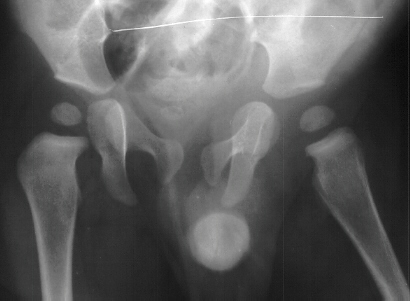

- 2 month Office Follow Up: Rt hip Xray: progressive destruction of capital

femoral epiphysis, cystic changes in metaphysis consistent with AVN.

- Age 6: Valgus osteotomy for subluxation and 2cm leg length inequality.

- Age 15: Valgus osteotomy for hip incongruity.

- Age 20: Hip arthroscopy. Hip fusion recommended.

This case is an example of untreated septic arthritis which caused avascular

necrosis of the proximal femur. The primary cause of this is undrained

septic hip. Repeated aspiration is not adequect treatment of a septic hip.